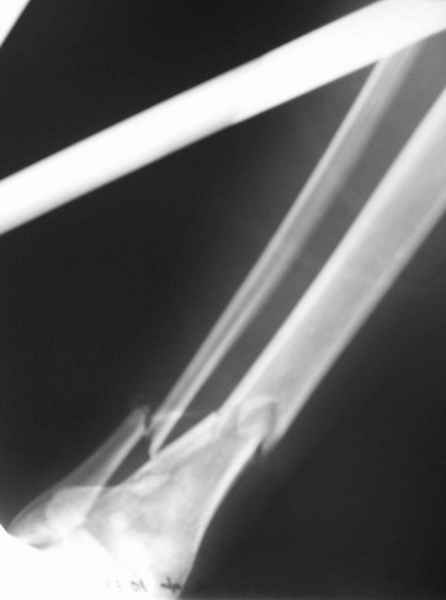

Открытый оскольчатый перелом н/3 голени.

Здравствуйте, коллеги! 16/10/06 г. В отделение поступила больная с производственной травмой - Открытый оскольчатый перелом метафиза и метадиафиза обеих костей правой голени со смещением отлоков.

При поступлении произведено ПХО ран, наложена система скелетного вытяжения за пяточную кость. Проводилась антибактериальная терапия, перевязки. На данный момент раны зажили первичным натяжением, швы сняты. Сохраняется лёгкая гиперемия в области одной из ран. Планируя оперативное лечение хотелось бы узнать Ваше мнение о наиболее рациональном методе лечения данного перелома.

Здравствуйте коллеги! В данной ситуации я полностью согласен с мнением Александра Николаевича! Практически любой внутрисуставной(тем более приведенный на снимках) перелом требует открытой репозиции.Судя по приведенным рентгенограммам, в области дистального тибио-фибулярного сочленения имеется "минус" ткань на tibia, которая может потребовать костной пластики.Метод фиксации любой,главное ранние движения в суставе. С уважением Руслан Ш.

К слову, тема этого обсуждения обозначена неточно, тут перелом дистального суставного конца типа 43-C, а не "открытый оскольчатый перелом н/3 голени", т.е. диафизарный, 42-.

Действительно, речь идет о сложном внутрисуставном, да еще и открытом переломе 43С.3.

1. Представленные рентгенограммы во-превых плохого качества (ну да ерунда), а во-вторых (самое главное) - в нестандартных проекциях. Невозможно оценить количество и положение фрагментов суставной поврехности. Собственно это делает обсуждение бессмысленным. Мы обсуждаем не конкретный случай, а вообще...